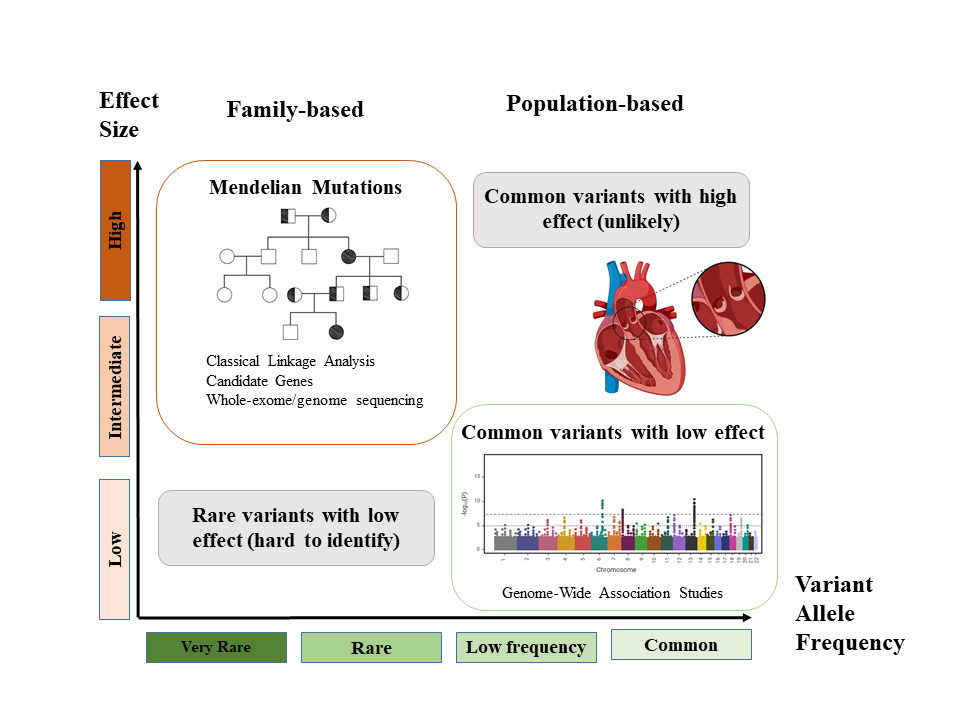

Traditionally, large families with well-documented histories have been crucial in determining the genetic basis of diseases thought genome-wide linkage analysis. However, with the advent of high-throughput technologies such as whole-exome and whole genome sequencing, as well as array comparative genome hybridization, the identification of new loci, associated genes, and chromosomal rearrangement has been accelerated. In vivo and in vitro functional studies have been decisive in dissecting molecular pathways. Nevertheless, the genetic research into valvulopathies is complicated by factors such as incomplete penetrance, phenotypic heterogeneity, and possible modifier factors which can obscure the genetic landscape of these diseases (Fig. 1).

Fig. 1.

Fig. 1.Genetic variants and human diseases. Variants with a high effect size are normally very rare and follow a Mendelian pattern of inheritance. In contrast, common variants in the general population have lower effects in the disease. Rare variants with low effect or common variants with high effect do not occur frequently.